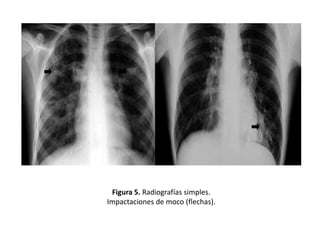

• Opacidades tubulares u ovoides (impactos

mucoides) que corresponden a bronquios

repletos de moco o líquido.

• En algunas ocasiones los bronquios, llenos de

secreciones, pueden visualizarse como

imágenes lineales densas en forma de Y, de V

o en dedo de guante. (Figuras 4 y 5)

Figura 5. Radiografías simples.

Impactaciones de moco (flechas).

Signos radiológicos • Opacidadestubulares u ovoides (impactos mucoides) que corresponden a bronquios repletos de moco o líquido. • En algunas ocasiones los bronquios, llenos de secreciones, pueden visualizarse como imágenes lineales densas en forma de Y, de V o en dedo de guante. (Figuras 4 y 5)

Figura 5. Radiografíassimples. Impactaciones de moco (flechas).